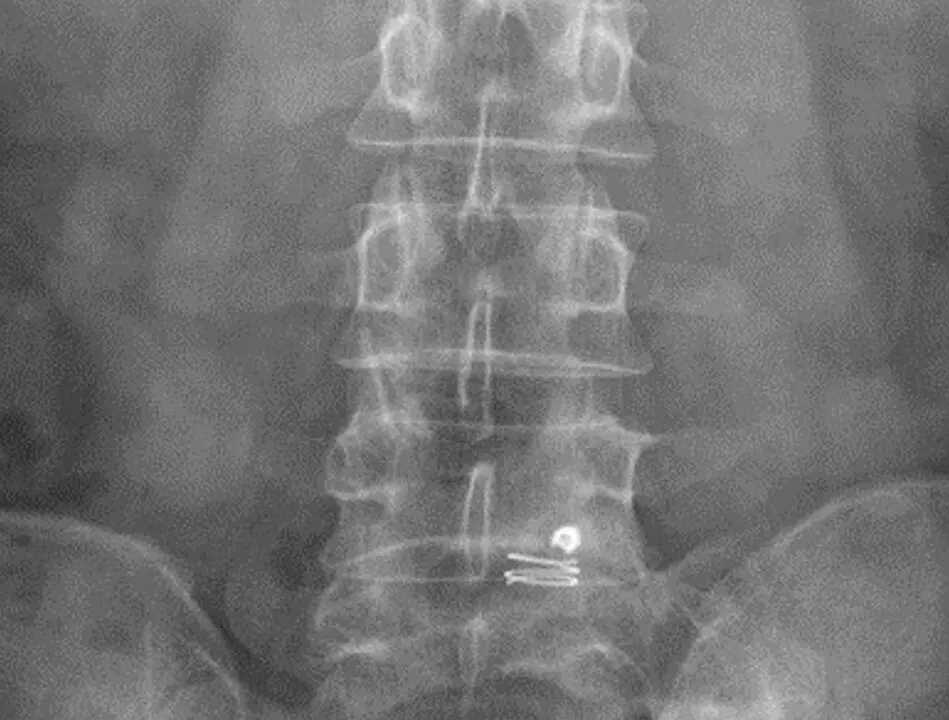

Tras extirpar una hernia, el principal riesgo es que esta vuelva a aparecer o que se deteriore el disco de la columna, pero este sistema bloquea el anillo fibroso del disco invertebral sin interferir en los movimientos naturales de la columna, según ha informado el Hospital de Bellvitge este viernes en un comunicado.

El estudio ha hecho un seguimiento de este sistema durante 6 meses en 30 pacientes con alto riesgo de reaparición de la hernia y todos ellos preservaron al menos el 75% de la altura inicial del disco y ninguno presentó degeneración del disco invertebral.